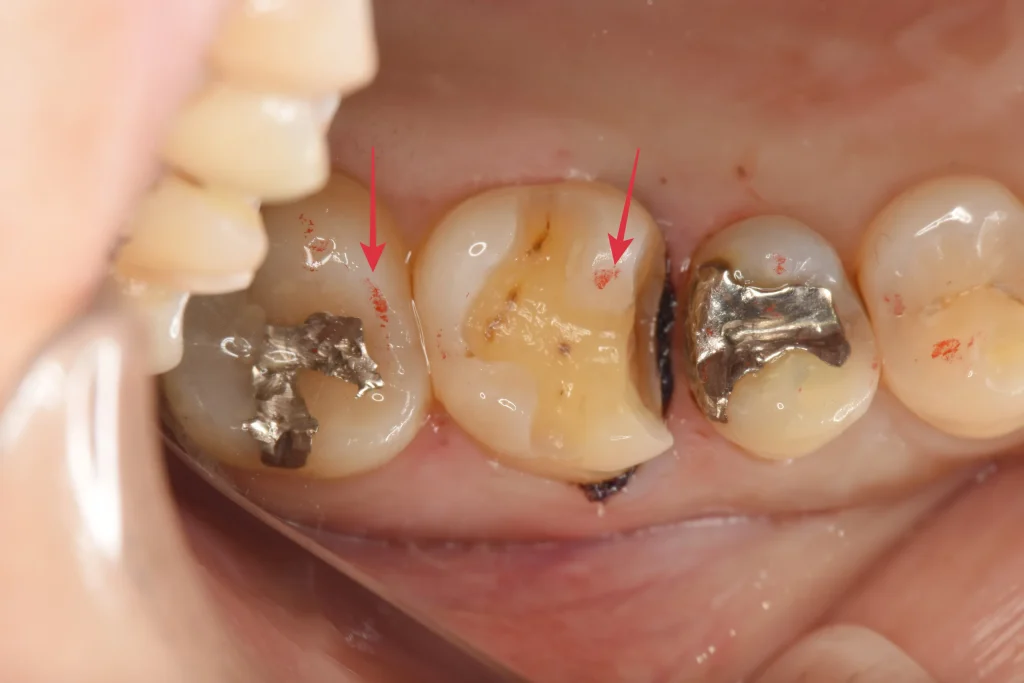

虫歯除去後、型取りの前です。赤印で、噛む位置の最終確認を行なっております。

e-maxはジルコニアに比べて割れる力に対して抵抗力が少ないため、噛む力が強い人は割れてしまう可能性があるため要注意です。